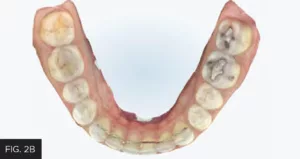

Once the orthodontic goal of the treatment plan was achieved, the restorative phase entailed the closure of the midline diastema and lengthening and recontouring of teeth #8 and 9. Itero (Align technology) scans of the maxillary and mandibular arches (FIG. 2A, 2B) were obtained from which diagnostic models were fabricated.

Scans of the mandibular and maxillary arches were obtained. Models were made from these and mounted. Wax-ups of the ideal restorative result were then fabricated on these mounted models.